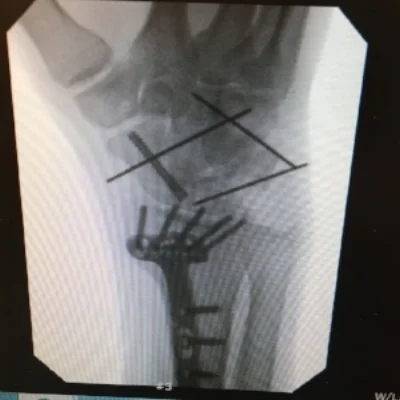

Miraculously, I ended up only breaking my wrist and having a minor concussion (too minor for Will Smith). Stillwater ER said I would be back on the bike in six weeks, but once I got a second opinion, I ended up needing surgery due to a dislocation and fracture in two places of the scaphoid.

x-ray 1.jpeg